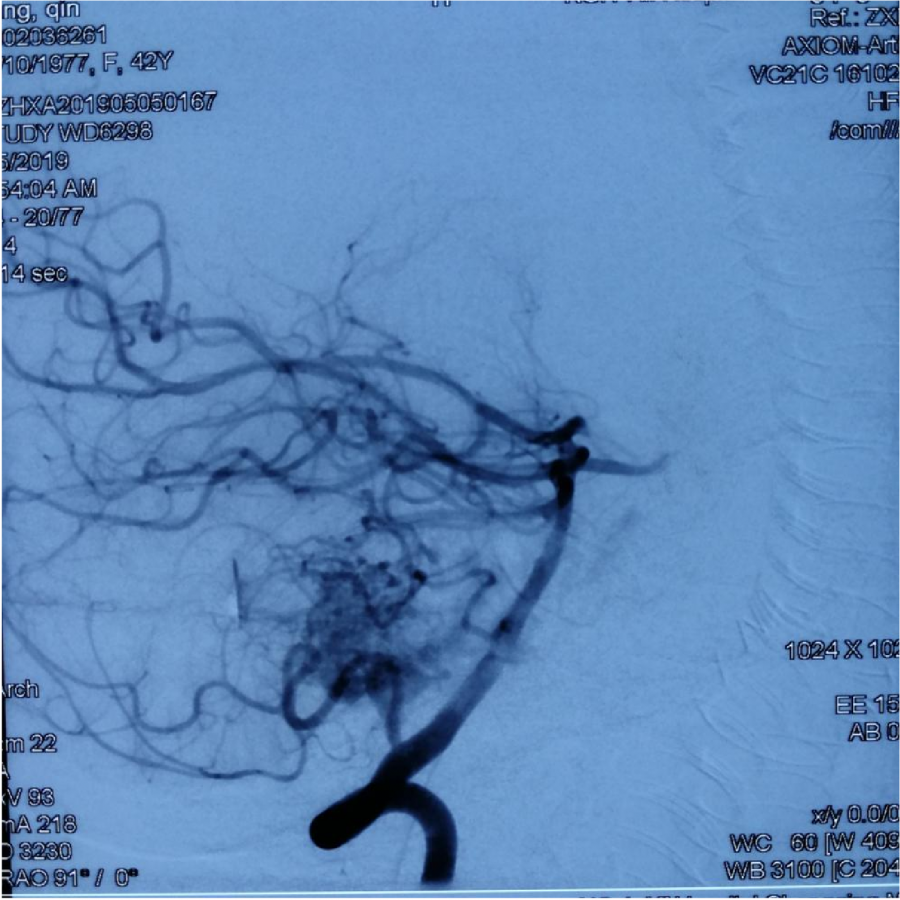

本次⼊院⾏DSA检查:PICA供⾎区有畸形⾎管团,引流到横窦

1、患者1年前⾏接⼊栓塞治疗,现仍有出⾎,且DSA显⽰PICA供⾎区仍有⼤量机型⾎管 团。

2、再次⾏接⼊栓塞治疗,路途不明确,且⼯学分散。

3、⾏伽⻢⼑治疗因畸形⾎管团皆在桥脑表⾯,且畸形⾎管团较分散,治疗困难。

4、综合考虑⾏开颅畸形⾎管团切除,然后再考虑下⼀步是否⾏伽⻢⼑治疗。